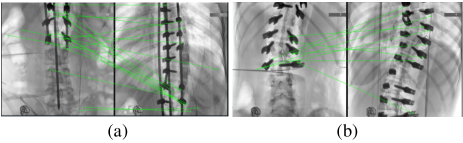

Refer to caption

Fig. 4: Qualitative Comparison on Multi-Image Stitching.

Multi-Image Stitching. Figure 4 clearly demonstrates the high accuracy of our stitching results in content alignment, and the progressive fusion technique applied effectively reduces some seams and parallax artifacts. The structure of the pedicle screws and fixation rods is clearly visible overall, which allows the physiological curvature and force line of the spine to be clearly displayed.